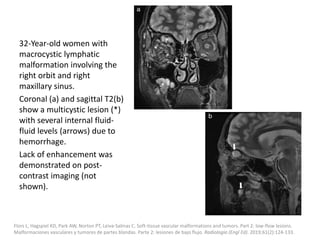

32-Year-old women with

macrocystic lymphatic

malformation involving the

right orbit and right

maxillary sinus.

Coronal (a) and sagittal T2(b)

show a multicystic lesion (*)

with several internal fluid-

fluid levels (arrows) due to

hemorrhage.

Lack of enhancement was

demonstrated on post-

contrast imaging (not

shown).